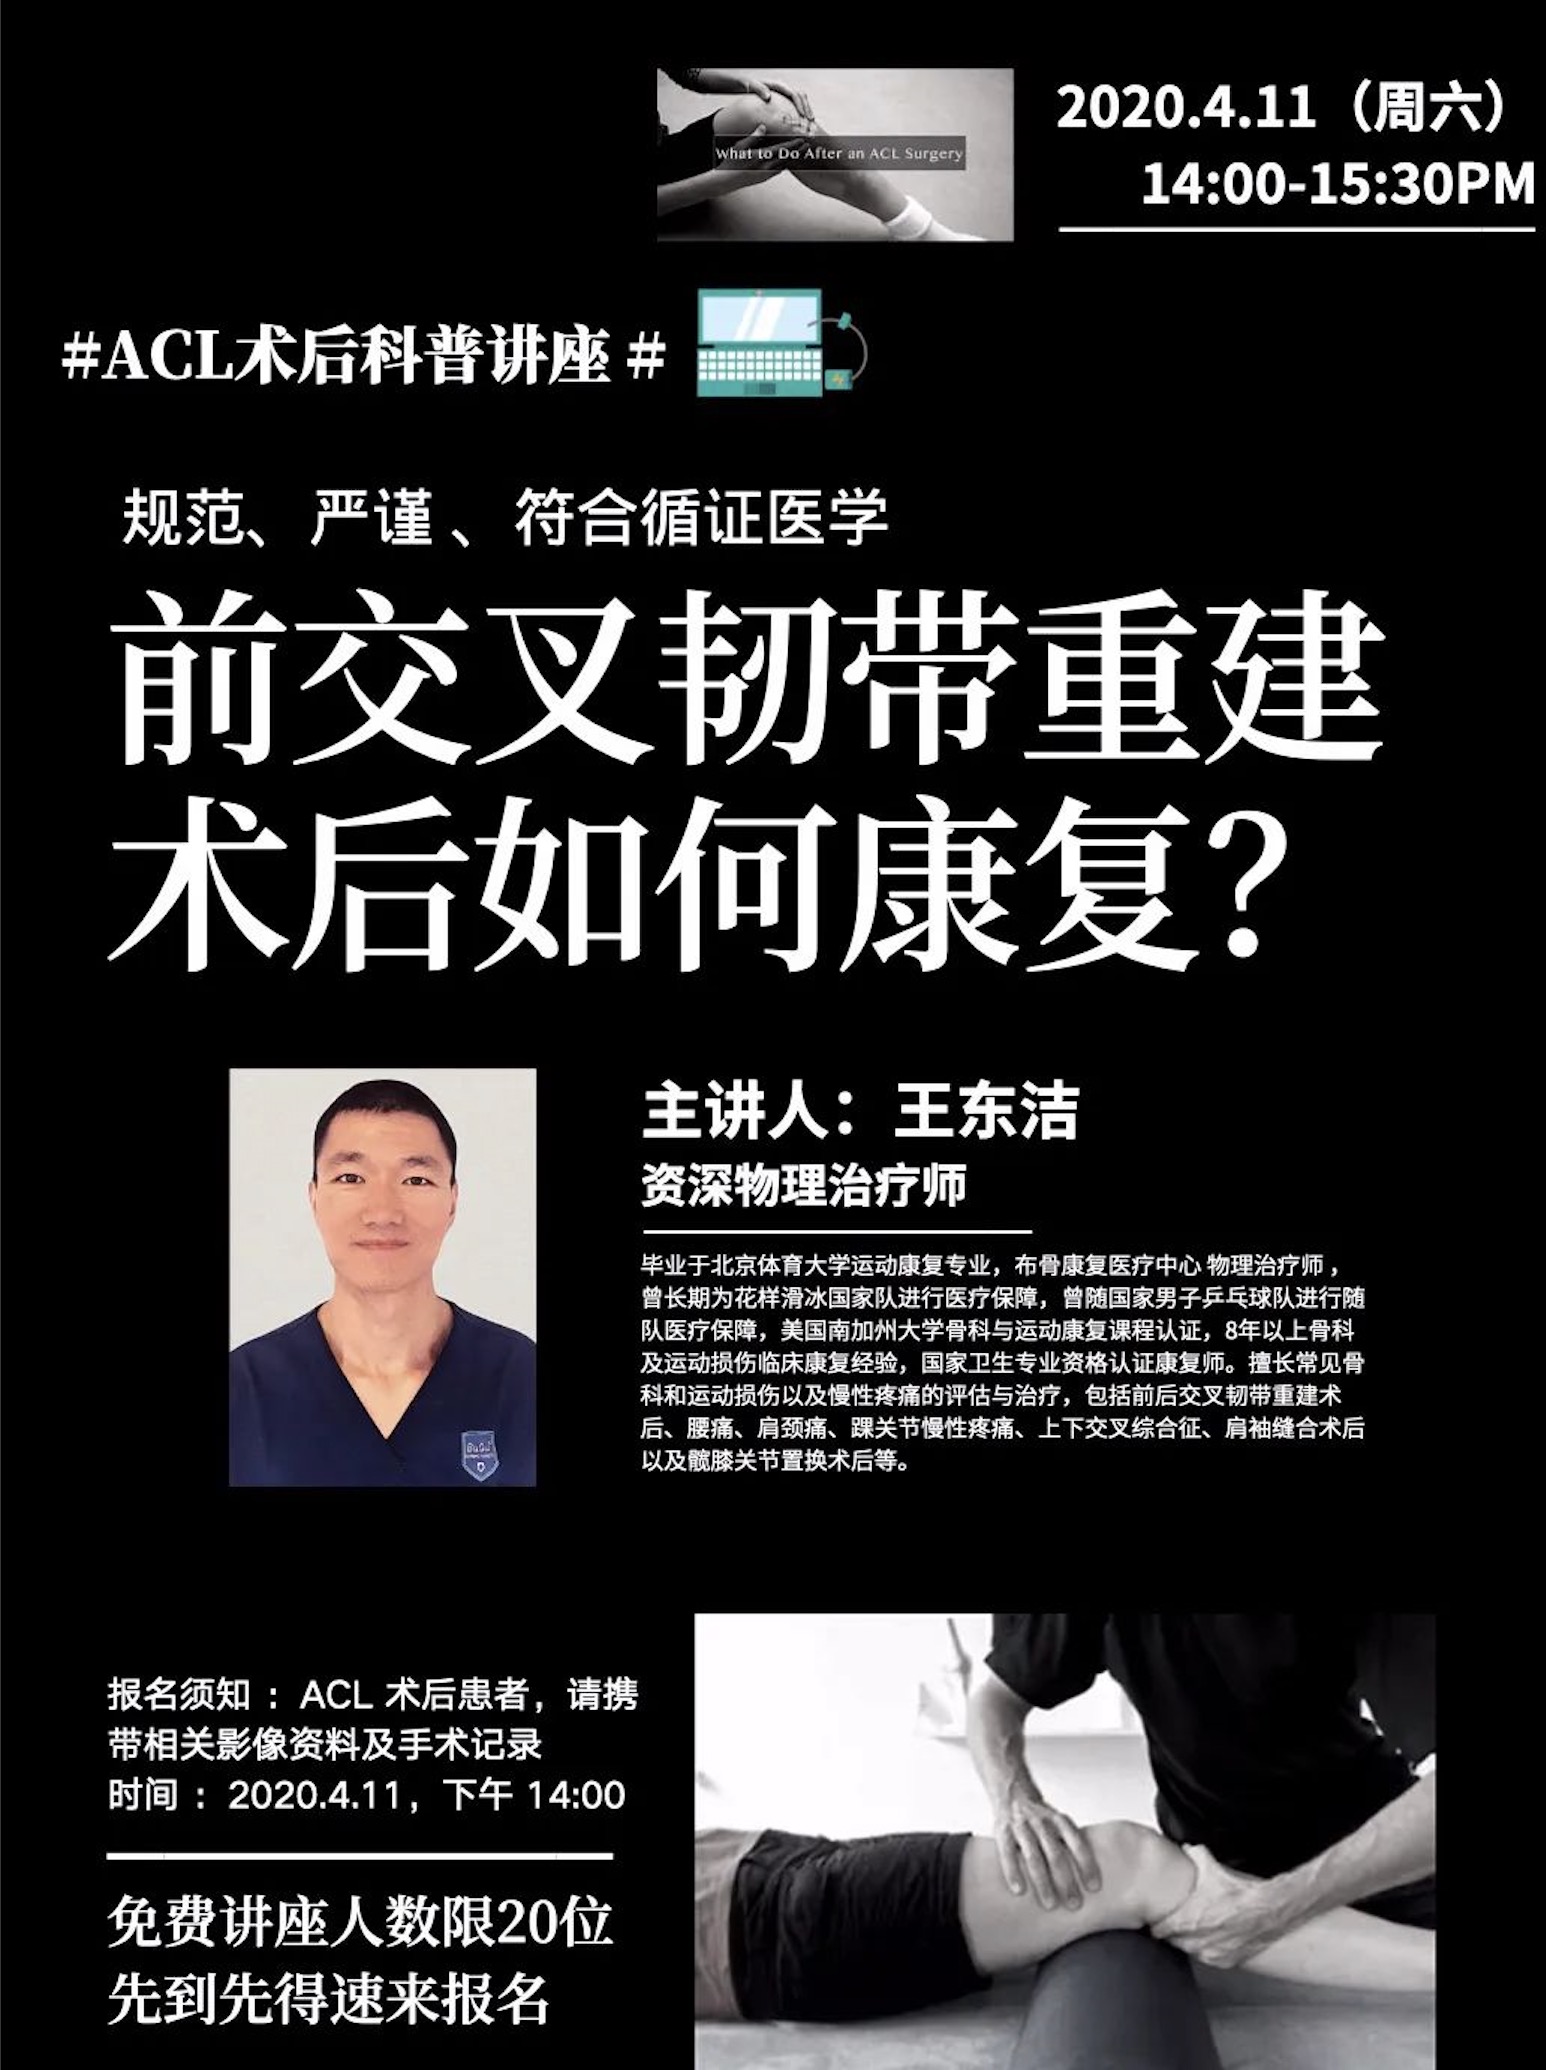

- 前交叉韧带重建术后康复、脊柱侧弯科普讲座,免费报名听干货! 布骨康复医疗中心 ,2020-04-05

- 在布骨康复医疗中心治疗过程中,发现一个特别突出的问题,康复意识和观念严重不足,其实良好的康复观念比康复治疗本身更为重要,良好的康复观念可以加速疾病的治愈。比如说,你患了颈椎病,不是仅仅解决目前的症状问题,更要后期纠正不良姿势,减少看手机的频率,适度进行颈椎周围肌肉和韧带的锻炼,否则,颈椎病就是伴随你.....